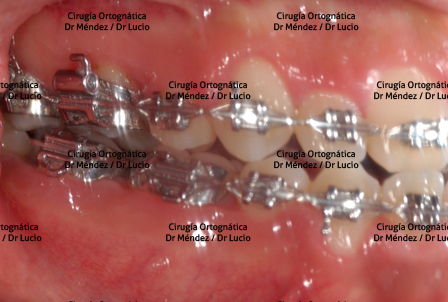

RETROGNASIA E HIPOPLASIA DEL MENTÓN Paciente operado de avance de mandíbula y mentoplastia de avance |

||